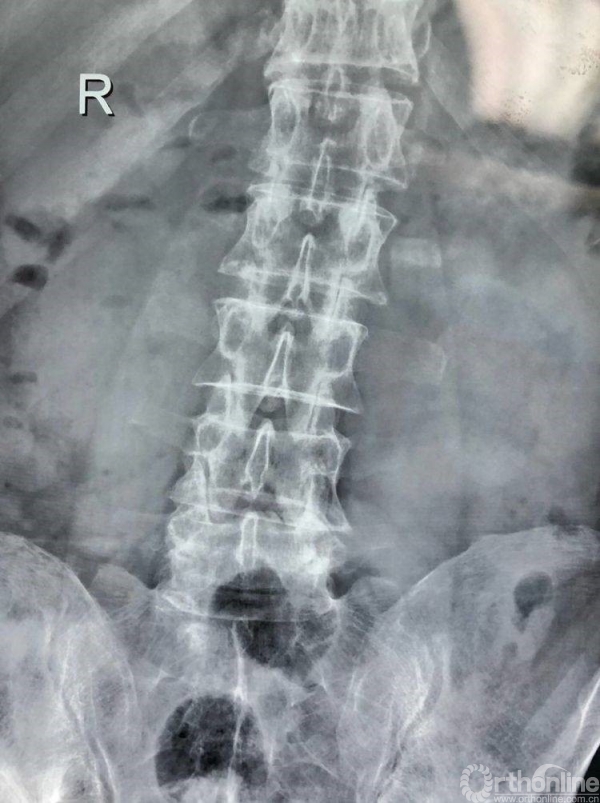

术前CT示L4/5重度椎管狭窄,腰椎滑脱合并硬膜囊受压。辅助检查如下:

正位X片